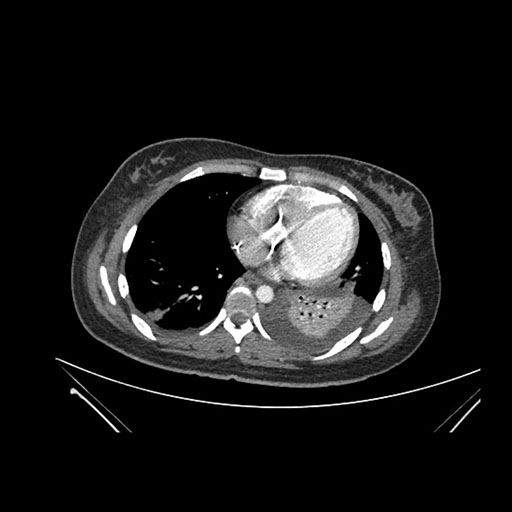

Look through the patient's CT scan to identify any areas of concern for the necessary procedure.

Axial Arterial

Axial Venous

Imaging analysis

Based on initial findings, which issue(s) would you be most concerned about?